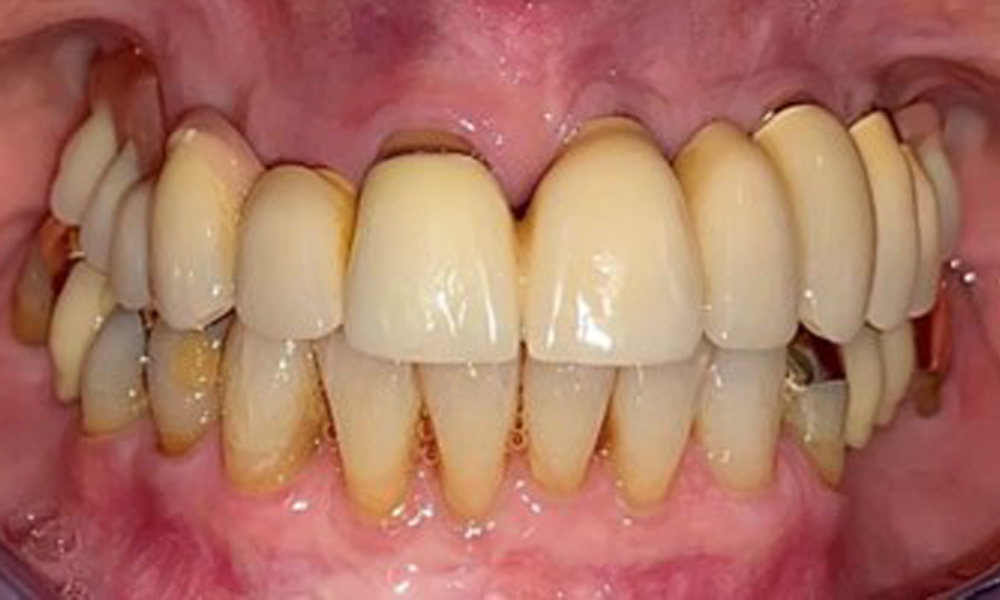

The dental findings are as follows: Combined removable implant and tooth-supported telescopic prostheses on implants 15, 13, 21, 23, 24, 25 and tooth 11 (Fig. 1, Fig. 2, Fig. 3). The patient was fitted with a fixed mandibular denture. Adequate bridges were present over 37 to 34 and 45 to 47 (Fig. 4), the crown margins were intact and there were no active caries. A composite filling with a marginal gap was present on tooth 43. There was mandibular gingival recession, exposing 1 to 3 mm of root surface. This also applies to 11.

Periodontal findings

The periodontal condition remains stable. There was no gingival or peri-implant soft tissue inflammation. At 1 to 3 mm, the probing depths were within the physiological range. There are generalised recessions measuring 1 to 3 mm. Implant 23 has an increased probing depth of 4 mm, although there are no signs of secretion or bleeding (Fig. 6). The total BOP is 12%.

The radiological findings show partially edentulous dentition with maxillary implants for teeth 15, 13, 21, 23, 24, 25 and a telescopic crown on tooth 11. Adequate mandibular bridges spanning 37 to 34 and 45 to 47 are present. 48 is impacted. There are suspected secondary caries distally on 43 and mesially on 44. 44 is restored with a non-radiopaque cavity lining. There is generalised horizontal bone loss of approx. 10% to 30% and localised vertical bone loss affecting teeth 22 and 42 (Fig. 5).